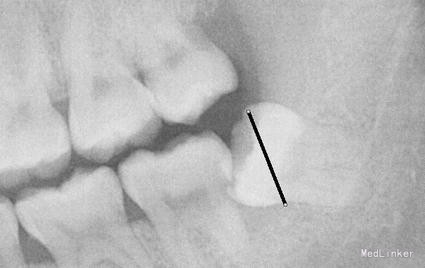

检查: 18.28颌面龋坏,质地软,牙颈部脱矿,叩诊(-),不松动。 37玻璃充填物,叩诊(-),不松动,冷热刺激正常。 38近中水平阻生,牙龈无红肿,叩诊(-),探诊有盲袋,盲袋内食物碎屑。 47缺失多年,48近中向移位,间隙1mm,叩诊(-),不松动。